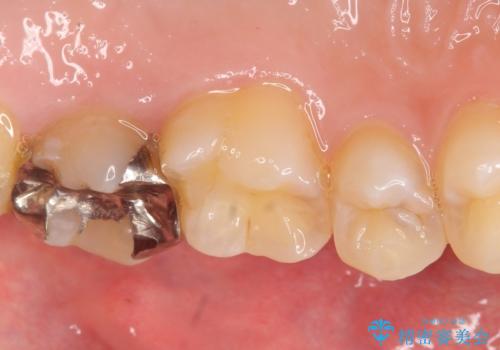

- 健診で虫歯があると言われたので診て欲しいといらっしゃった方の症例です。

左上5、6、7番目の歯に虫歯を認めたため、左上5、7はセラミックインレーによる修復を行いました。

左上6に関しては患者様の希望でパラジウムインレーによる修復を行いました。